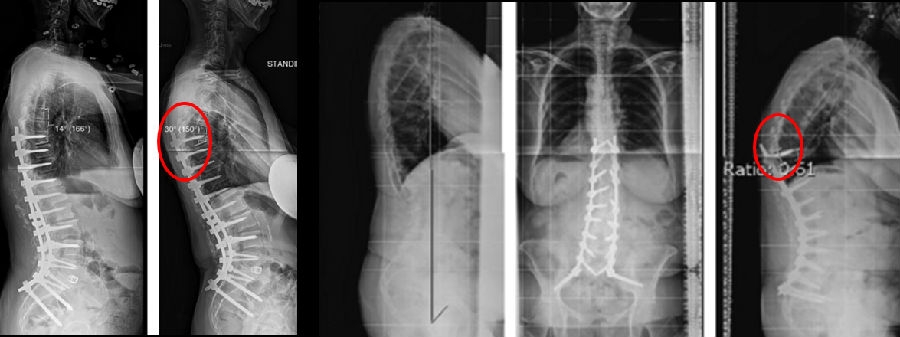

图18 固定近端交界性后凸角>5°

A:术前固定近端交界性后凸角>5°;B:上固定椎未跨过此区域;C:术后随访出现PJK

Ø 颈7铅垂线距离UIV太远

图19 颈7铅垂线距离UIV太远

Ø 上固定椎在上终椎的尾端

图20 Lenke 1型脊柱侧弯上固定椎(UIV)选择在上端椎(UEV)的尾端是导致PJK的危险因素

Ø 术后PI-LL不匹配,PI-LL大于10°

图21 术后PI-LL不匹配,大于10°